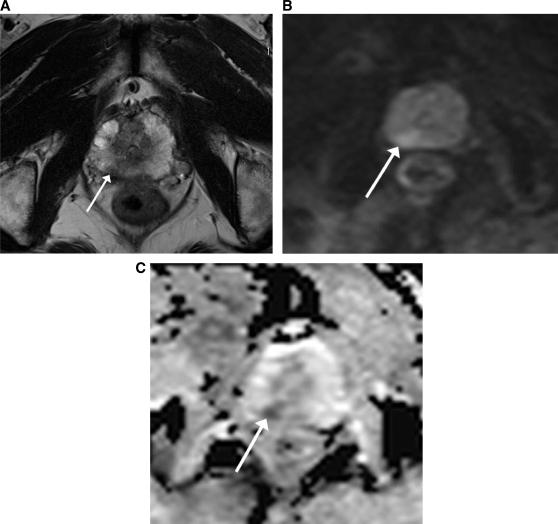

Diffusion-weighted magnetic resonance imaging (DW-MRI) appears to hold promise as a non-invasive imaging modality in the detection of early microstructural and functional changes of different organs. DW-MRI is an imaging technique with a high sensitivity for the detection of a large variety of diseases in the urogenital tract. In kidneys, DW-MRI has shown promise for the characterization of solid lesions. Also in focal T1 hyperintense lesions DW-MRI was able to differentiate hemorrhagic cysts from tumours according to the lower apparent diffusion coefficient (ADC) values reported for renal cell carcinomas. Promising results were also published for the detection of prostate cancer. DW-MRI applied in addition to conventional T2-weighted imaging has been found to improve tumour detection. On a 3 T magnetic resonance unit ADC values were reported to be lower for tumours compared with the normal-appearing peripheral zone. The combined approach of T2-weighted imaging and DW-MRI also showed promising results for the detection of recurrent tumour in patients after radiation therapy. DW-MRI may improve the performance of conventional T2-weighted and contrast-enhanced MRI in the preoperative work-up of bladder cancer, as it may help in distinguishing superficial from muscle invasive bladder cancer, which is critical for patient management. Another challenging application of DW-MRI in the urogenital tract is the detection of pelvic lymph node metastases. As the ADC is generally reduced in malignant tumours and increased under inflammatory conditions, reduced ADC values were expected in patients with lymph node metastases.

弥散加权磁共振成像(DW-MRI)似乎有望成为一种非侵入性的成像方式,用于检测不同器官的早期微观结构和功能变化。DW-MRI 是一种对泌尿生殖系统多种疾病具有高灵敏度的成像技术。在肾脏中,DW-MRI 已显示出对实体病变进行特征描述的潜力。在局灶性 T1 高信号病变中,DW-MRI 也能够根据报告的肾细胞癌较低的表观扩散系数(ADC)值,将出血性囊肿与肿瘤区分开来。在前列腺癌的检测中也取得了有前途的结果。DW-MRI 与常规 T2 加权成像联合应用已被发现可提高肿瘤检测的灵敏度。在 3T 磁共振仪上,与正常外观的外周带相比,肿瘤的 ADC 值较低。T2 加权成像和 DW-MRI 的联合应用也显示出在放射治疗后检测复发性肿瘤方面有很好的效果。DW-MRI 可能会改善常规 T2 加权和对比增强 MRI 在膀胱癌术前评估中的性能,因为它可能有助于区分表浅性和肌层浸润性膀胱癌,这对患者管理至关重要。DW-MRI 在泌尿生殖系统中的另一个具有挑战性的应用是检测盆腔淋巴结转移。由于 ADC 通常在恶性肿瘤中降低,而在炎症条件下升高,因此预计淋巴结转移患者的 ADC 值会降低。